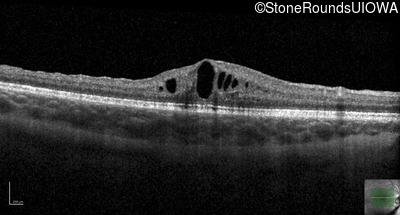

XL Retinoschisis (IIIB1)

Age at visit: 9 years

Age at visit: 11 years